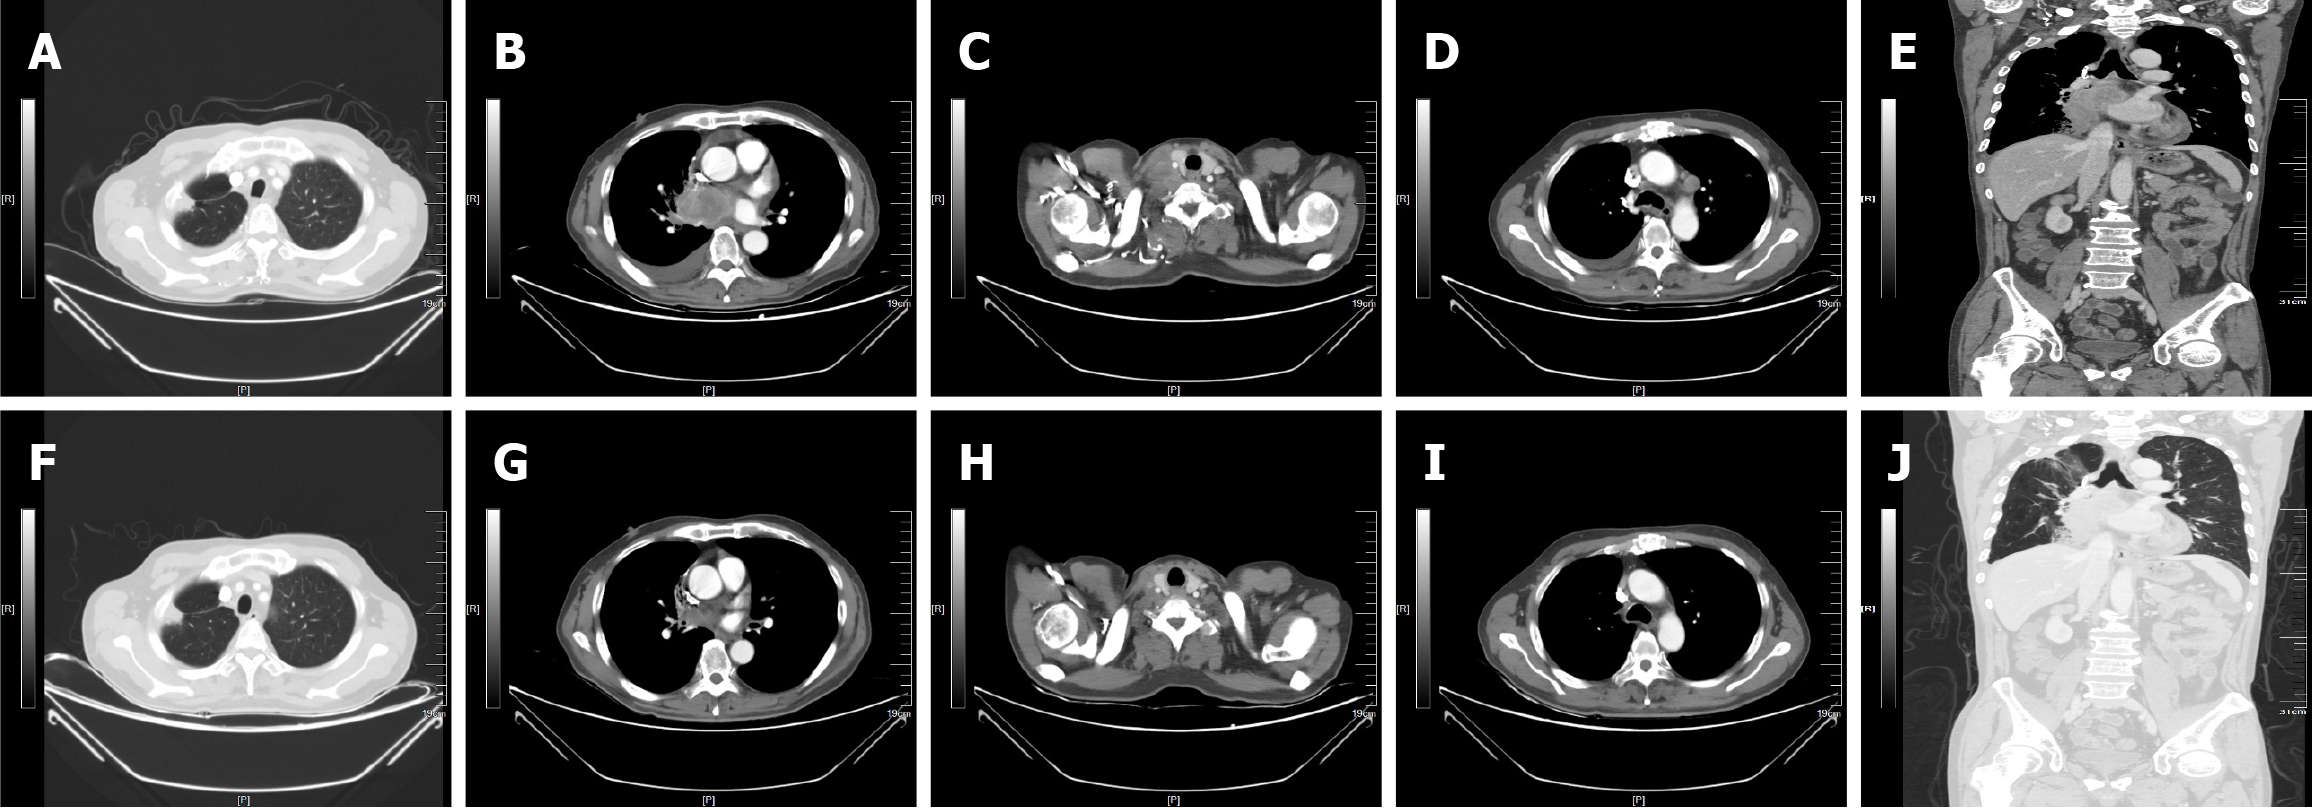

Figure 1 Contrast-enhanced computed tomography images.

A-E: Lung window; A: The images show the local nodular thickening of the right pleura; B: The mass film shadow near the right lung portal; C: The images show the pleural effusion; D: The images show the cervical lymph nodes metastasis; E: Coronal observation shows that the mediastinal lymph nodes are enlarged; F-J: Mediastinal window; F: The images show the local nodular thickening of the right pleura; G: The mass film shadow near the right lung portal; H: The images show the pleural effusion; I: The images show the cervical lymph nodes metastasis; J: Coronal observation shows that the mediastinal lymph nodes are enlarged.